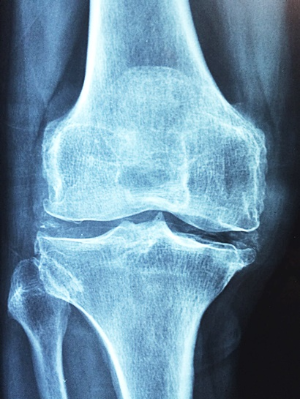

우선, 관절이란 두 개 이상의 뼈가 연결되어 움직임을 가능케 하는 부위입니다. 이는 연골, 인대, 힘줄, 관절낭 등 복합적인 구조로 이루어져 있어, 우리의 일상 움직임과 기능을 원활하게 유지하는 데 중요한 역할을 합니다.

3. 관절 부음

류마티스 관절염은 주로 양쪽의 대칭적인 작은 관절을 표적으로 합니다. 손가락, 발가락의 관절, 손목, 발목, 팔꿈치, 무릎 등이 부어오르고 아프며 따끔거립니다. 이런 부음은 염증으로 인해 관절 주변의 활막이 팽창하고 관절액이 증가하기 때문입니다.